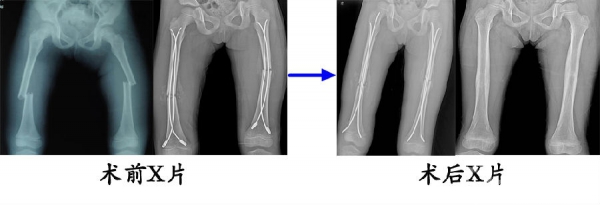

12.6岁,女,双侧股骨干骨折,在外院初次手术(髓内针直径过小,尾帽使用不当)复位不成功,来我院翻修(调整弹性髓内针直径,去除尾帽),翻修术后8个月,骨愈合良好,拆除弹性髓内针。